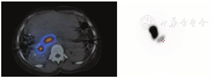

首次术后随访应该在治疗后1~3个月进行,采用腹部增强CT或MR,虽然术后3~6个月才是最佳观察时期[9]。尽管肿瘤在2种影像上表现不同,但治疗反应的特征相似[46]。如果治疗成功,则随着肿瘤血管的减少,肿瘤的大小和增强将减弱,范围与肿瘤坏死相一致(图6)。MRI的弥散受限将增加,因坏死组织的细胞膜完整性受损。经过90Y微球选择性内放射治疗后,一部分肿瘤大小可能反常增加;但是,任何大小的增加通常都是继发于周围正常肝实质细胞的死亡,不应错误地解释为肿瘤生长。治疗后影像复查中的另一个需要注意的陷阱是坏死腔周围的环形强化,有时它会被误解为肿瘤残留,但实际上它代表了肿瘤治疗后的纤维化。如果进行随访PET显像,则提示病灶缩小和代谢下降。术后成像还可以评判是否发生90Y微球选择性内放射治疗后并发症。